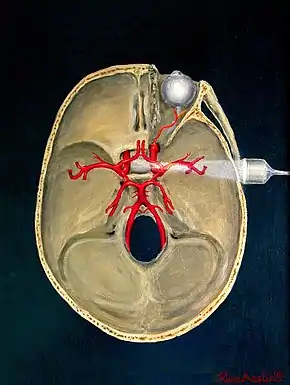

Transcranial

Transcranial Doppler (TCD) and transcranial color Doppler (TCCD) measure the velocity of blood flow through the brain's blood vessels transcranially (through the cranium). These modes of medical imaging conduct a spectral analysis of the acoustic signals they receive and can therefore be classified as methods of active acoustocerebrography. They are used as tests to help diagnose emboli, stenosis, vasospasm from a subarachnoid hemorrhage (bleeding from a ruptured aneurysm), and other problems. These relatively quick and inexpensive tests are growing in popularity. The tests are effective for detecting sickle cell disease, ischemic cerebrovascular disease, subarachnoid hemorrhage, arteriovenous malformations, and cerebral circulatory arrest. The tests are possibly useful for perioperative monitoring and meningeal infection.[6] The equipment used for these tests is becoming increasingly portable, making it possible for a clinician to travel to a hospital, to a doctor's office, or to a nursing home for both inpatient and outpatient studies. The tests are often used in conjunction with other tests such as MRI, MRA, carotid duplex ultrasound and CT scans. The tests are also used for research in cognitive neuroscience.